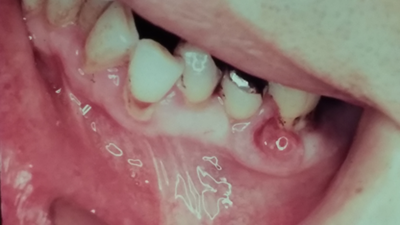

症例

奥歯の表側に見える小さな腫脹は口腔がんで、院長が診断したものです。

これは肺がんから歯ぐきに転移した非常に珍しい症例でした。

そのため日本口腔科学会で発表し、日本口腔外科学会雑誌に収載され、多数の他の論文に引用されました。